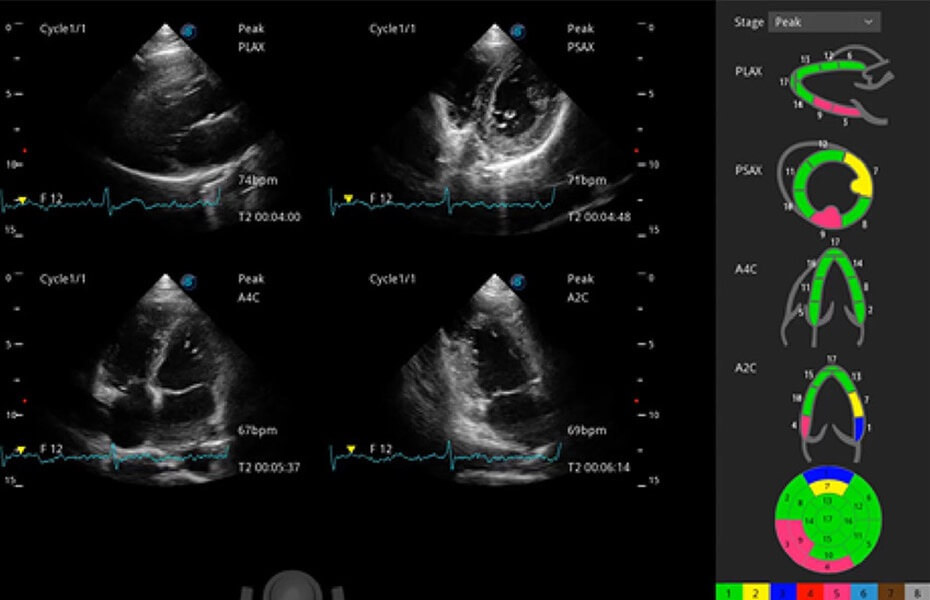

• Stress Echo 負(fù)荷超聲心動(dòng)圖

具備多種協(xié)議可選,同時(shí)支持17階段劃分法和專(zhuān)業(yè)的SE報(bào)告。